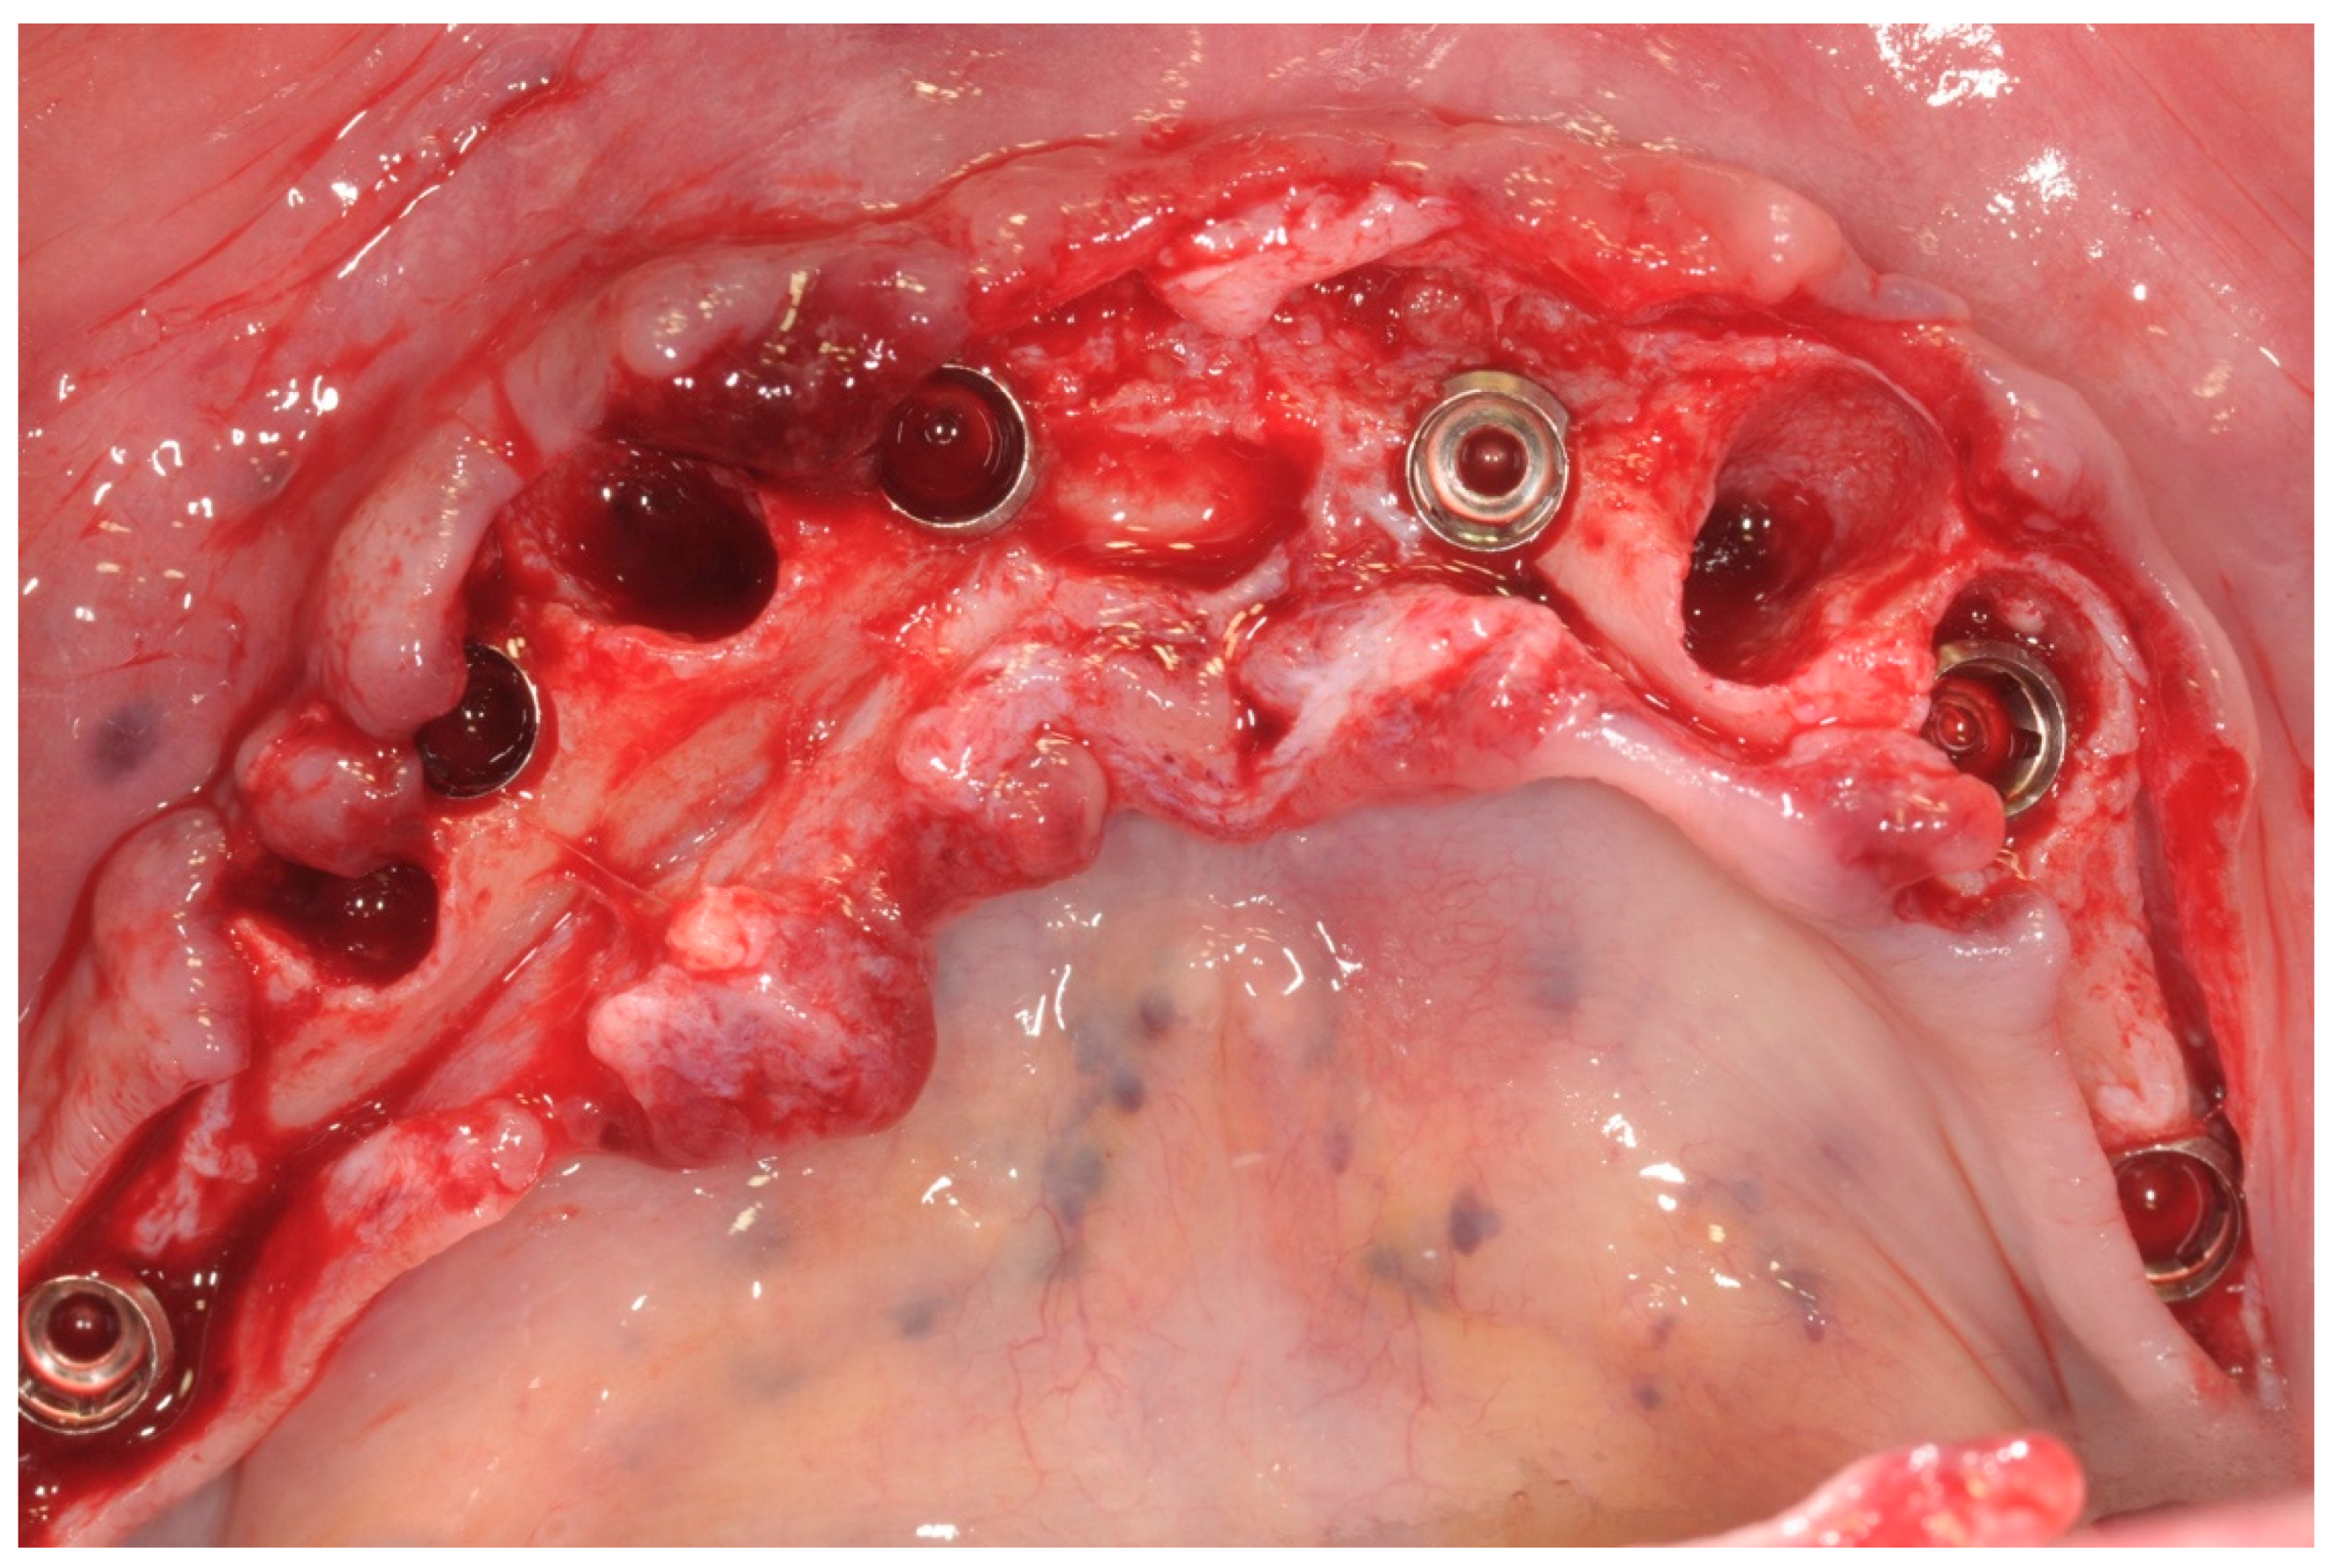

All patients were treated under local anesthesia, and patients received four, five, or six implants in the mandible according to the prosthetic treatment plan. In the case of tooth extraction sites, a periodontal probe was used to assess the integrity of the extraction socket’s bony walls and of the adjacent bone peaks to evaluate the feasibility of an immediate implant (Figure 2).

All patients received implants with a grit-blasted and acid-etched surface (Ossean®; Intra-Lock International®, Inc., Boca Raton, FL, USA) that were placed using a sterile surgical technique, as recommended by the manufacturer. Maximum care was taken to place the implants, regardless of whether they were inserted in an edentulous ridge or an extraction site, with a minimum insertion torque of 35 Ncm and not exceeding 50 Ncm (Figure 3).

The peri-implant bone defects in the extraction sockets were grafted with a cortico-cancellous porcine bone (GTO, Tecnoss-Dental, Giaveno, Italy). Flat abutments (FlatOne®; Intra-Lock International®, Inc., Boca Raton, FL, USA) were then connected to the implants, and the flap was sutured (Figure 4).

Figure 4. Flat abutment connection.